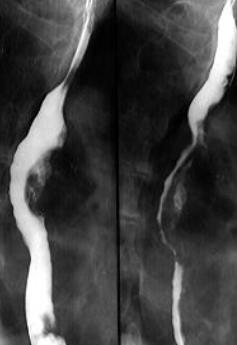

Diverticuli medioesofagieni

Diverticul medioesofagian